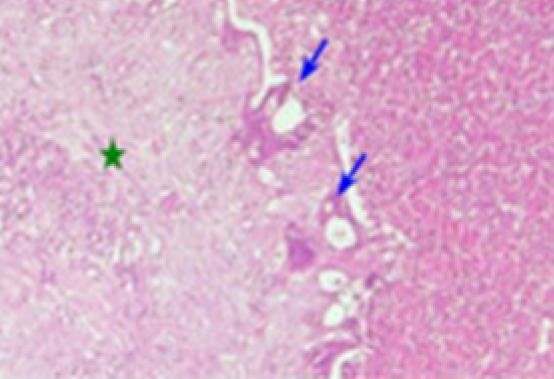

Methods: A retrospective monocentric study including patients with CRLM operated after neoadjuvant treatment. Assessment of histological response was based on the Rubbia-Brandt tumor regression grading score. The scores were grouped into two types of response: Response Group (R) and No Response Group (NR).

Results: The study included 77 patients (mean age=56 years, sex ratio=1.57). Node metastases were noticed in 62% of cases. Synchronous liver metastasis was present in 42 cases (55%) and metachronous liver metastasis in 45%. Neoadjuvant treatment consisted of CT only in 52 patients (68%) and CT with targeted therapy in 25 patients (32%). Chemo-induced lesions were present in 44 patients (57%). Histological response was presented (Group R) in 36 cases (47%) and absent (Group NR) in 41 cases (53%). The overall survival of our patients was 32 months. For Group R, survival was significantly greater (p=0.001). The predictive factors of histological response identified were delay in the onset of liver metastasis greater than 14 months (p=0.027) and neoadjuvant treatment combining CT and targeted therapy (p=0.031). In multivariate analysis, the type of neoadjuvant treatment (p=0.035) was an independent predictive factor of histological response.